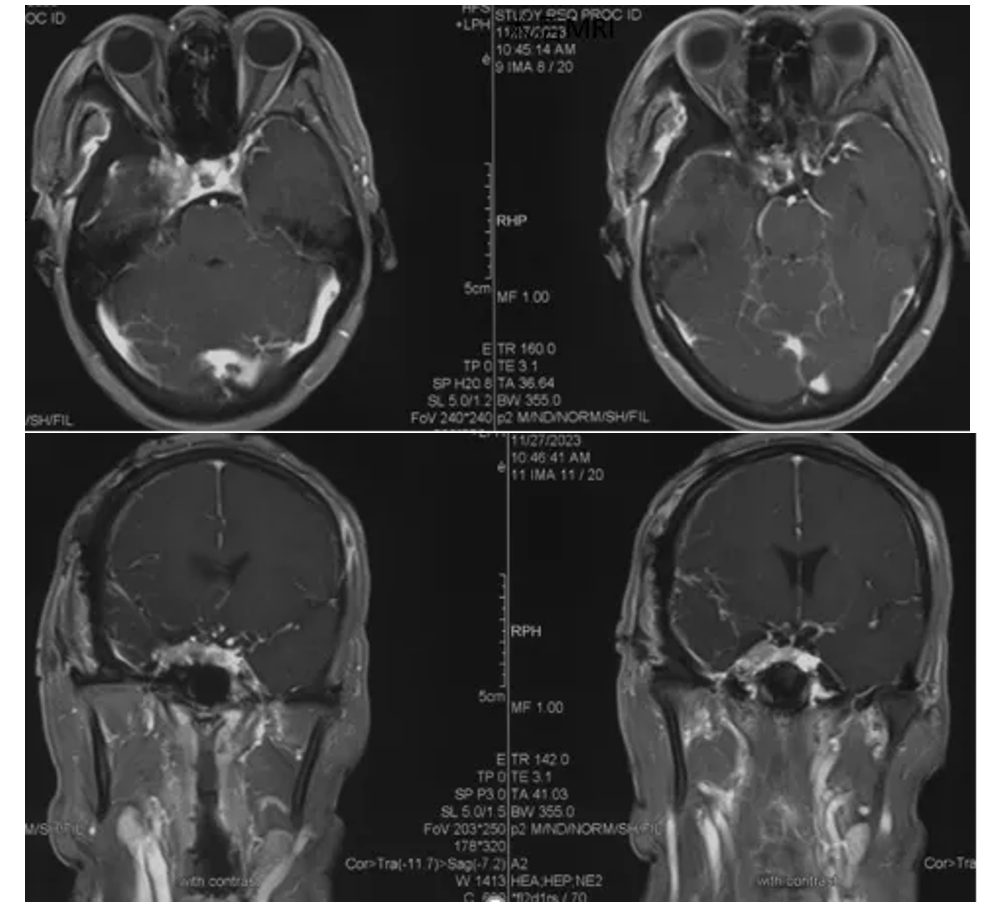

Postoperative MRI enhancement

Showing complete resection of the tumor.